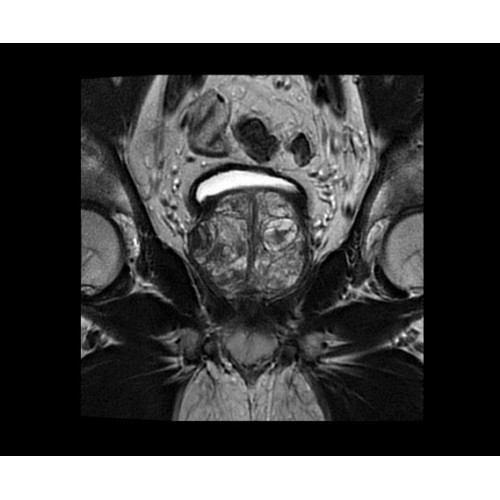

SIGNA PET/MR 3.0T — это гибридная система, в которой совмещаются две принципиально разные технологии — магнитно-резонансную томографию (МРТ) и позитронно-эмиссионную томографию (ПЭТ). Система отличающийся высокой чувствительностью и эффективностью и предназначена для диагностики в области онкологии, неврологии, кардио-васкулярных исследований, исследований воспалительных процессов.

Компания GE Healthcare представляет революционную, полностью интегрированную систему SIGNA PET/MR1, в которой сочетаются времяпролетная технология (TOF) и возможности напряженности магнитного поля 3.0 Тл. Мы поможем вам поднять исследования на более высокий уровень. SIGNA PET/MR позволяет достичь впечатляющей точности и скорости исследований, а благодаря новейшей технологии реконструкции Q.Clear2 качество изображений улучшается в два раза. Кроме того, в систему включен полный набор клинических приложений и гибких катушек для проведения любых видов исследования, открывая для вас возможности визуализации, о которых вы даже не догадывались.

• МРТ с функцией нулевого времени эхо (ZTE) отличается точностью, возможностью персональных настроек и отсутствием ионизирующего излучения. Она приходит на смену традиционному исследованию на основе рентгеновского излучения. МРТ с функцией нулевого времени эхо (ZTE) на базе SIGNA ПЭТ/МРТ является более надежной и быстрой по сравнению с системами, использующими сверхмалое время эхо (UTE).